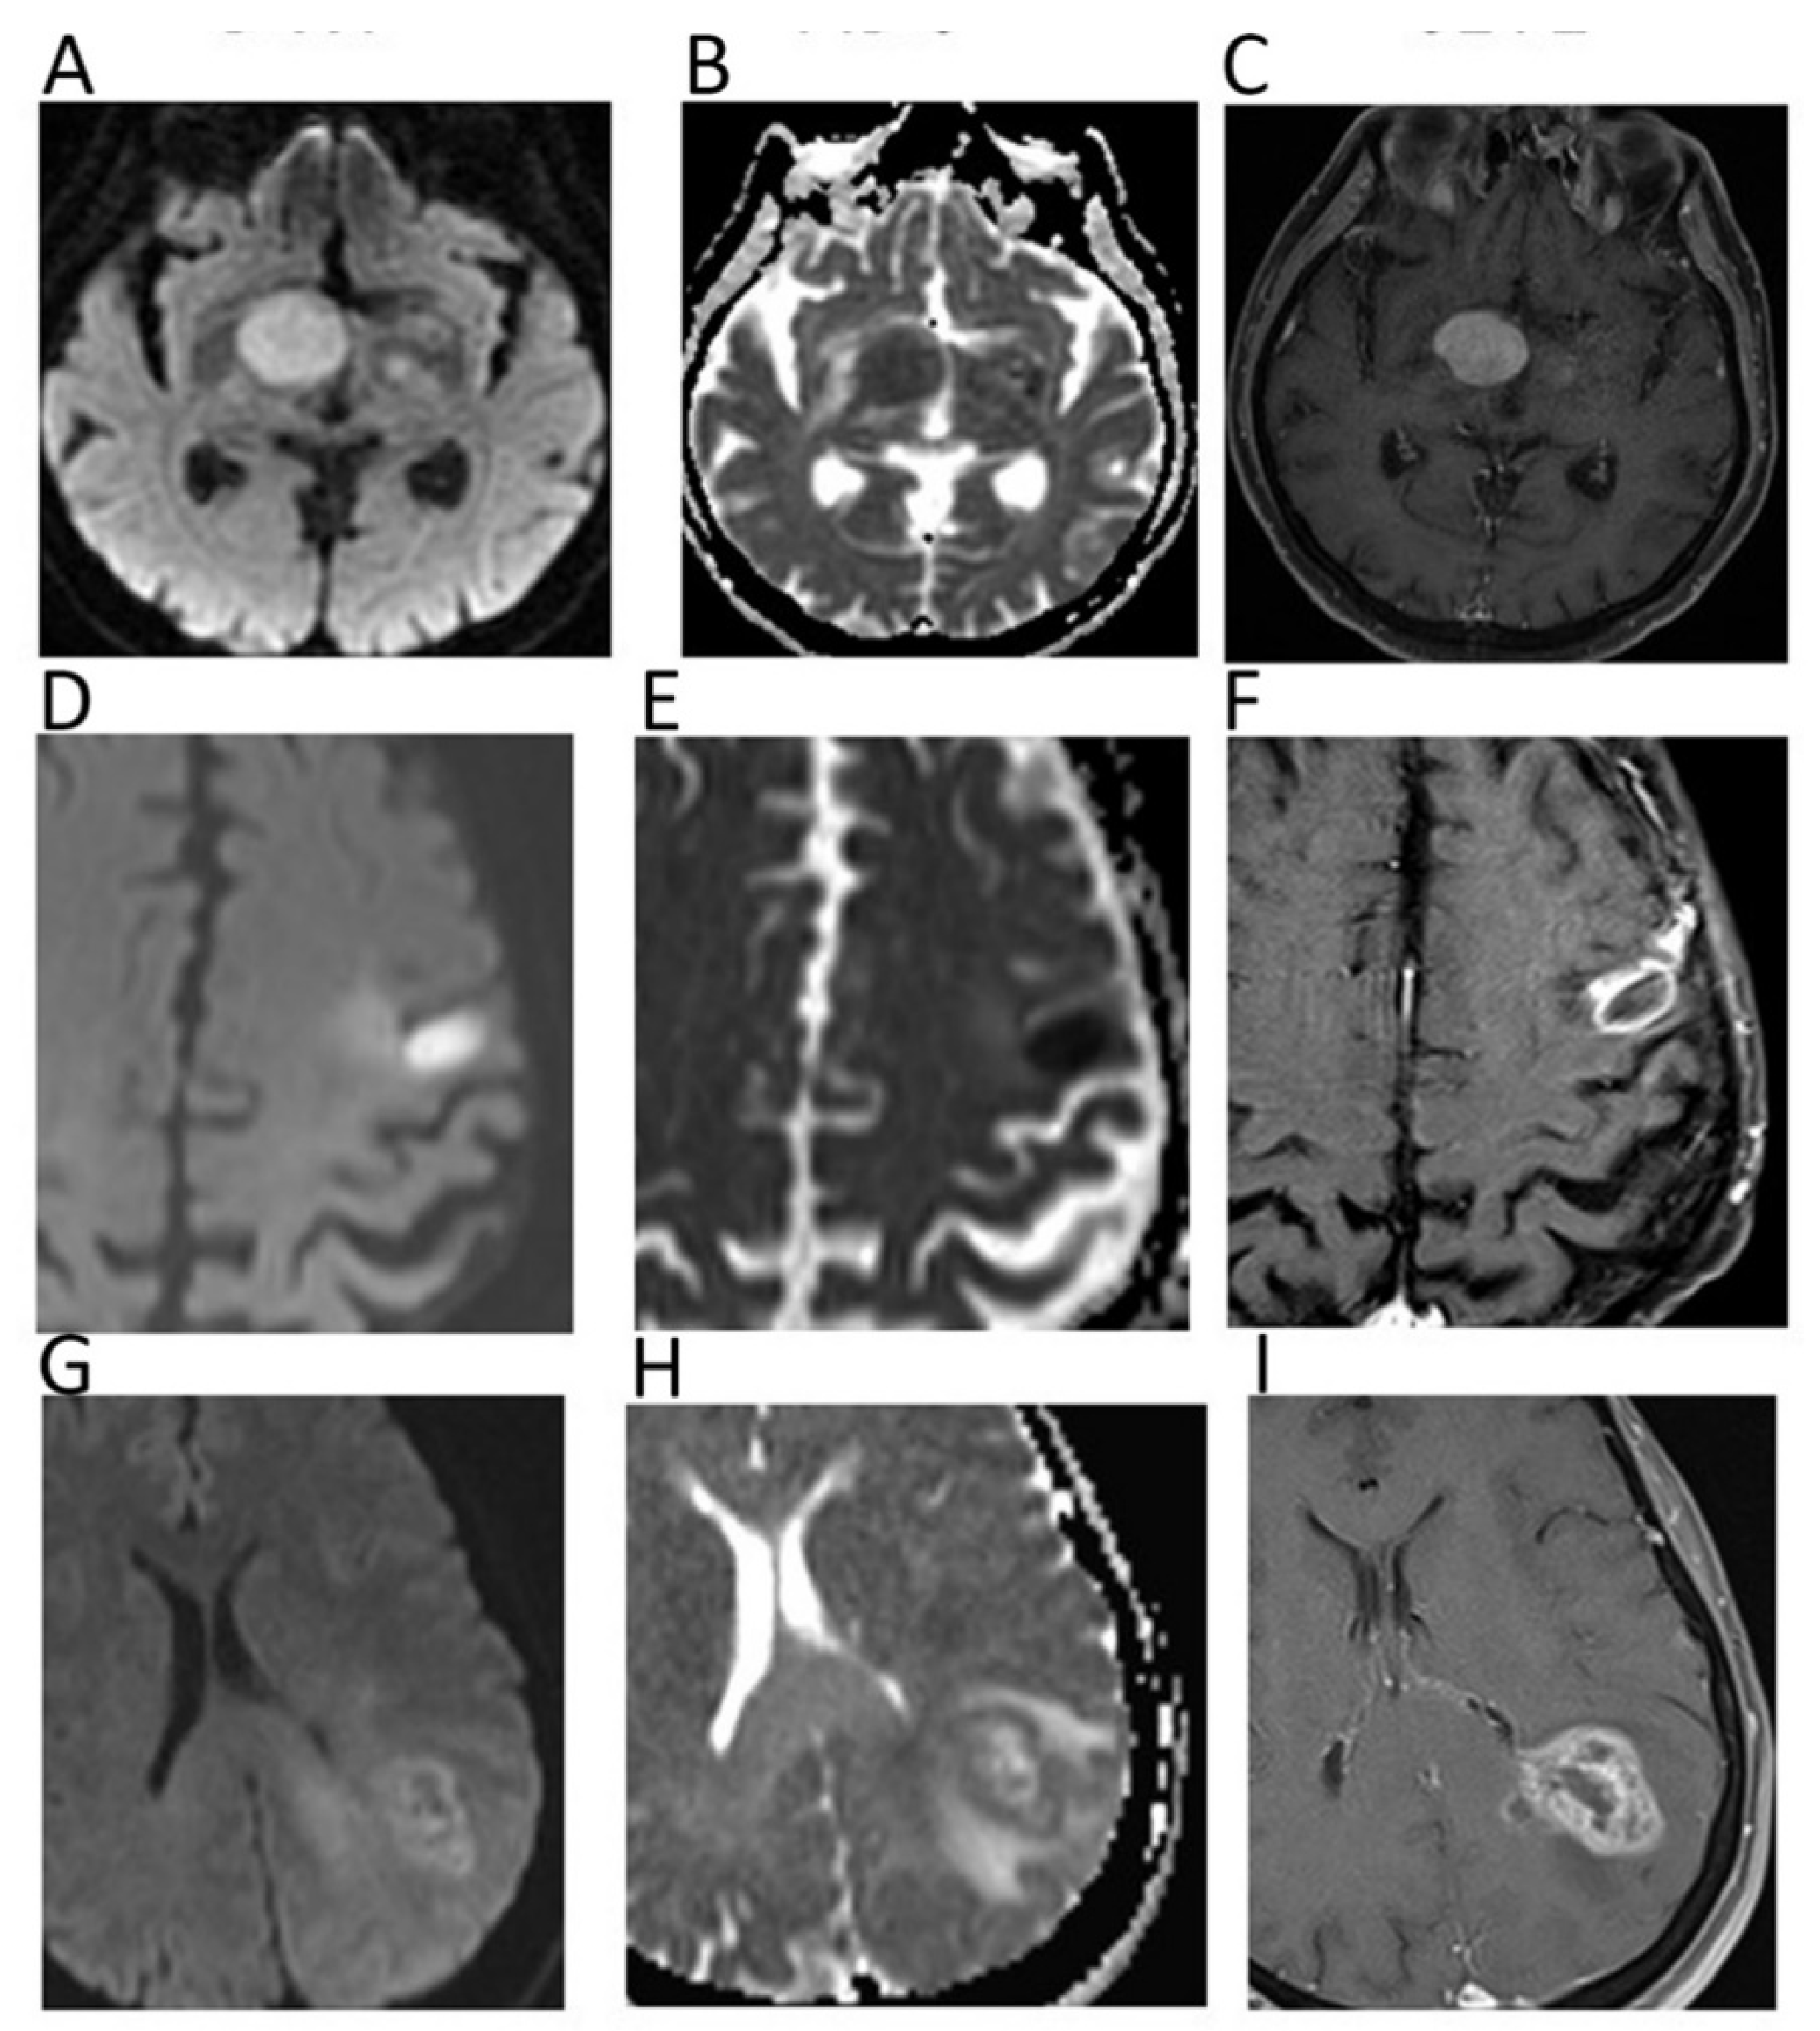

DWI is included in routine brain tumor MRI protocol, generally including two b-values (b = 0, b = 1000 s/mm2). While conventional sequences are useful for mass detection, DWI helps achieving the diagnosis, providing information regarding tumor grade and type, and monitoring the treatment response [1]. DWI can differentiate abscesses, presenting impeded diffusion and low ADC (0.28–0.73 × 10−3 mm2/s), from necrotic tumors, showing higher ADC (Figure 1) [2].

Figure 1.

Diffusion weighted imaging (DWI) b = 1000 images (A,D,G), corresponding apparent diffusion coefficient (ADC) maps (B,E,H), and contrast–enhanced T1 w images (C,F,I) of patients with histologically proven primary central nervous system lymphoma (A–C), cerebral abscess (D–F), and glioblastoma (G–I). Mean ADC values in lymphoma (0.648 × 10−3 mm2/s) and in the central portion of the abscess (0.510 × 10−3 mm2/s) were lower than in glioblastoma. In particular, mean ADC values were higher in the necrotic core of the GBM (1.082 × 10−3 mm2/s) in comparison to the abscess.

With regard to tumor type, low ADC suggests a hypercellular malignancy such as lymphoma, which presents lower ADC compared to high-grade gliomas (HGGs) and metastases (Figure 1) [1]. The ADC of dysembryoplastic neuroepithelial tumors was reported to be higher than that of astrocytic tumors, while ADC of medulloblastoma is generally lower than that of ependymomas and posterior fossa astrocytomas [3]. Thus, ADC can be helpful in narrowing the differential diagnosis for both adult and paediatric intracranial masses. Due to their cellular content, low-grade gliomas usually present higher ADC compared to HGGs, although a certain overlap between the two groups has been observed [1]. Indeed, despite their high cellularity, HGGs are heterogeneous, presenting necrotic components with higher ADC. In this setting, intravoxel incoherent motion (IVIM) and diffusional kurtosis imaging (DKI) are emerging DWI applications, with the former allowing one to separately estimate tissue diffusivity and microcapillary perfusion, while the latter can analyze non-Gaussian diffusion through high diffusion weighting [4].